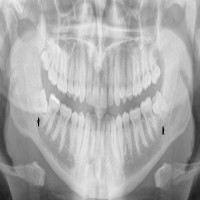

دندان عقل معمولاً آخرین دندانی است که در سنین ۱۷ تا ۲۵ سالگی رشد میکند. در بسیاری از افراد، فضای کافی برای رشد صحیح دندان عقل وجود ندارد؛ به همین دلیل ممکن است به صورت نهفته یا نیمهنهفته باقی بماند، باعث درد، التهاب لثه، پوسیدگی دندانهای مجاور یا حتی آسیب به عصب فک شود.

• مشاوره تخصصی و بررسی دقیق عکس رادیولوژی